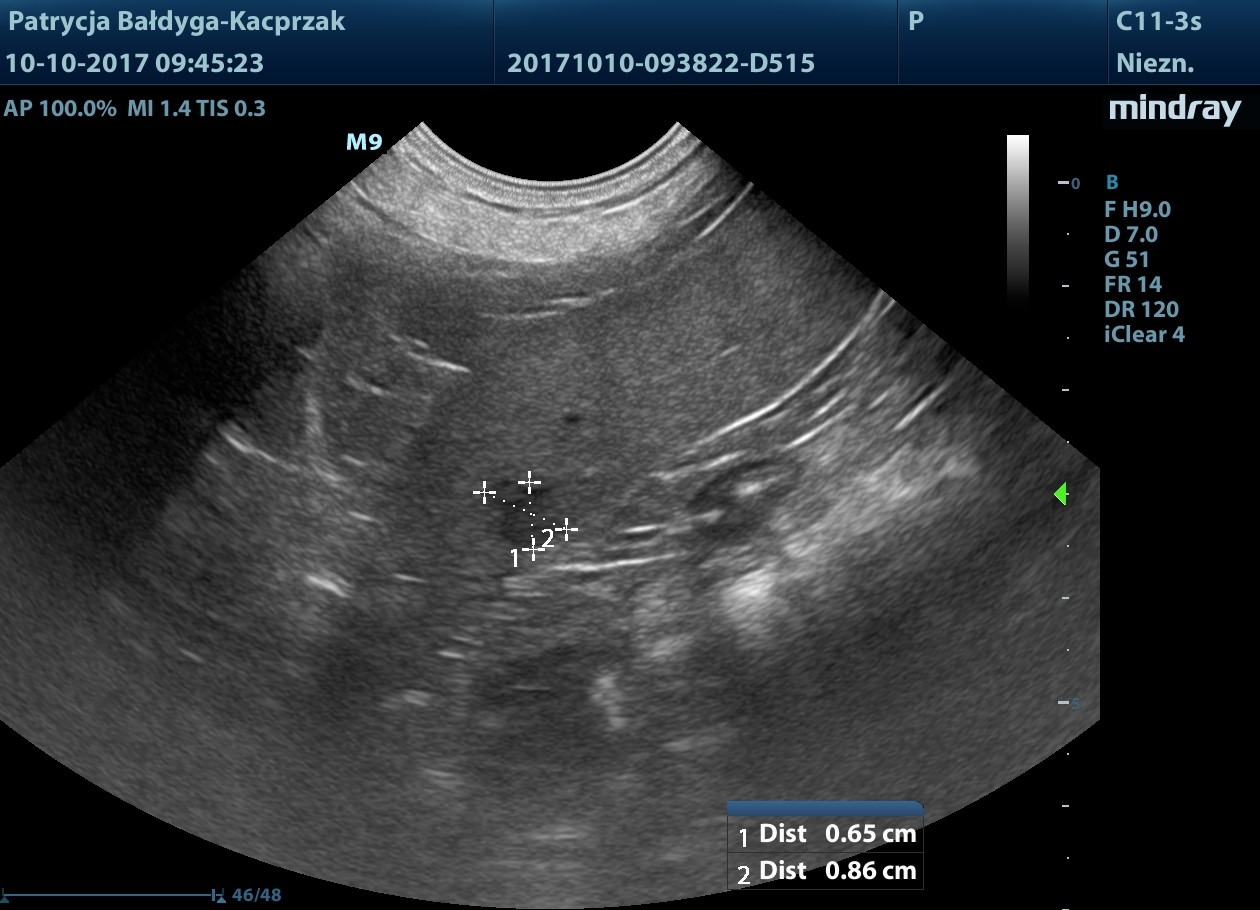

naciekowa, śródścienna, hipoechogenna, niesymetryczna 6-18 mm, dł. 2,5 cm, warstwowość w tym miejscu zatarta, obecny okoliczny, nieznaczny odczyn zapalny (pod koniec filmu 3), ww, chłonne okrężnicze środkowe reaktywne, powiększone, hipoechogenne, zokrąglone, śr. ok. 7-8 mm